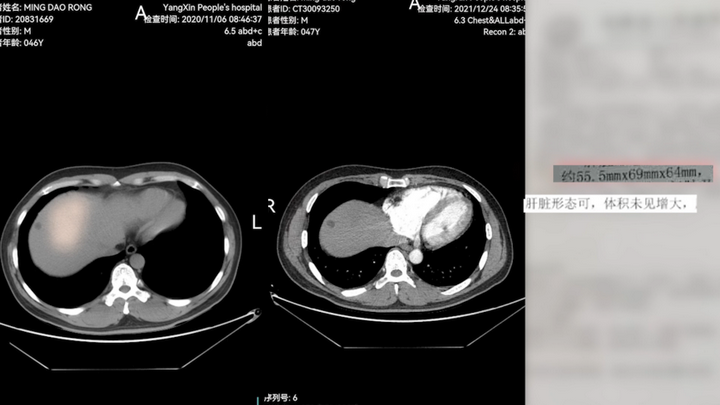

53岁的明叔(化名),带着表弟和邻居,坐了十几小时硬座从湖北来到北京。这条路他两年没走了,但无比熟悉——2年前,他被诊断为弥漫性肝癌晚期,癌肿大如鸭蛋,并被当地医院断言生命仅剩3个月。

绝望中,明叔找到了钟伟主任。在“靶向+免疫+中药”的治疗方案下,奇迹悄然发生。服药10天,明叔腹部的胀痛开始减轻;1个月后复查,肿瘤缩小了1cm多;4个月后再检,肿瘤缩至2cm多。到2021年底,肝部肿瘤全部消失。